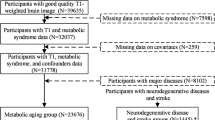

To set up a supervised machine learning framework, we split the data from 21,382 individuals into four sets: a training (N = 3,067), validation (N = 3,962), healthy test (N = 2,057) and unselected (general) population test (N = 12,296) set. Individuals were divided randomly between the four sets, subject to restrictions on the number of apparently healthy and unhealthy individuals in each set. Healthy participants were defined as those who did not report health conditions or chronic treatments for health conditions and hospital ICD coding available through UK Biobank did not identify chronic disease at the time of, or preceding, baseline assessment. The training set was used to optimise parameters of the neural network and learn relationships between healthy brain structure and age. This allowed the model to learn a representation of the physiological age-related modifications in brains of healthy individuals as a proxy for changes occurring with normal aging processes. Including brains from unhealthy individuals would have forced the model to learn structural changes related to disease and correct its predictions accordingly. The validation set was used to tune and assess the model without exposing it to individuals reserved for the final analysis.

We used two separate hold-out test sets to evaluate model performance. The former containing only healthy individuals to test the model on unseen healthy individuals. The latter test set was used for conducting the phenome-wide association study and included individuals who had not been stratified for health status. See Supplementary Table 1 for descriptive characteristics of each data set.